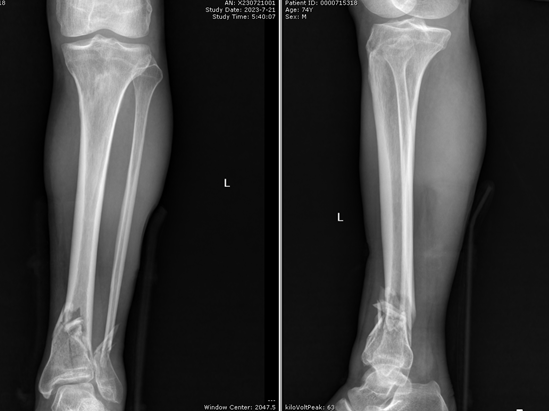

近日,湘雅常德医院骨科病房收治一位74岁高龄、左下肢胫腓骨远端粉碎性骨折的患者谭爷爷。入院时,谭爷爷左小腿严重肿胀,骨折远端外翻畸形,爷爷非常焦虑,他害怕本次受伤会让本不富裕的家庭雪上加霜,甚至一度产生了放弃治疗的想法。在骨科医护人员的共同安慰下谭爷爷才安下心来接受住院治疗。我院骨科创伤组杨雷主治医师及陈治佑主治医师第一时间接诊了该患者,予以石膏外固定制动以避免二次损伤、口服药物消肿补钙治疗。

对于胫腓骨粉碎性骨折的手术治疗,一般临床共识考虑行双钢板系统固定,需在小腿内外侧行2道纵行长切口。但此种手术耗时长,对机体损伤较大,且存在中间皮肤坏死可能。而且谭爷爷年龄较大,并有肺气肿、冠心病病史,长时间手术易造成心脑血管意外。身形消瘦,皮肤营养差、弹性差的他,发生皮肤坏死概率较年轻人更大。